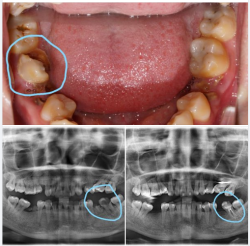

Nhiều bệnh nhân, và kể cả bác sĩ, đã từng nghĩ rằng "chiếc răng này làm sao giữ lại nổi?"

Ủa ủa, có gì đâu mà giữ không nổi? Giữ răng thật của bệnh nhân là mục tiêu quan trọng nhất của một người nha sĩ! Điều trị và giữ được những chiếc răng...